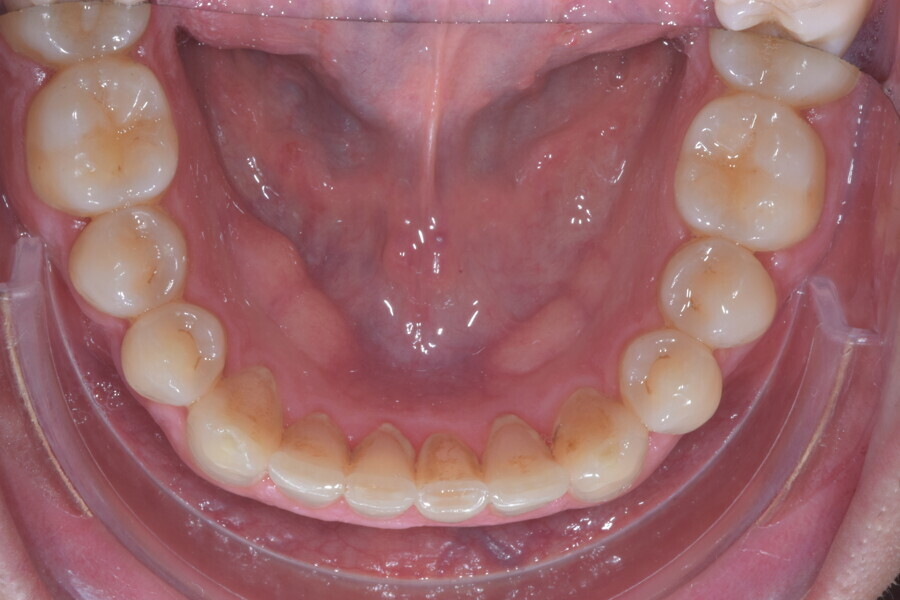

En raison de l’âge du patient, les aligneurs ont été changés tous les dix jours, dans le cadre d’un traitement d’une durée inférieure à six mois. À la fin de la première série d’aligneurs, un nouveau plan de traitement numérique comportant cinq autres aligneurs a été conçu, en vue d’améliorer l’intercuspidation des molaires sans élastiques. (Photos : Dr Alessandro Greco)

Le plan de traitement numérique (ClinCheck) avait prévu douze aligneurs pour l’arcade maxillaire et dix-sept pour l’arcade mandibulaire. Les objectifs du traitement visaient à combiner les mouvements verticaux d’extrusion des dents postérieures et les mouvements d’intrusion des dents antérieurs, au moyen de rampes d’occlusion, tout en utilisant des taquets d’extrusion pour assurer la désocclusion des dents postérieures et l’intrusion des dents antérieures inférieures, nécessaires au nivellement de l’arcade mandibulaire. La courbe de Spee a été nivelée et le profil plat ainsi que la position des lèvres ont été améliorés par une vestibulo-version des incisives supérieures et inférieures. Le plan avait prévu des élastiques de classe II pour faciliter la vestibulo-version des dents inférieures et les puissants contacts occlusaux postérieurs, avec une extrusion relative des dents postérieures. Une morphologie plus large de l’arcade et une intercuspidation idéale ont été obtenues par des mouvements de torque proches de 0° des dents latérales et postérieures supérieures. Aucune conception technique excessive n’avait été prévue dans le plan de traitement numérique. En raison de l’âge du patient, les aligneurs ont été changés tous les dix jours, dans le cadre d’un traitement d’une durée inférieure à six mois. À la fin de la première série d’aligneurs (Figs. 20–24), un nouveau plan de traitement numérique comportant cinq autres aligneurs a été conçu, en vue d’améliorer l’intercuspidation des molaires sans élastiques. La durée totale du traitement a donc été prolongée jusqu’à 7,5 mois puisque les aligneurs supplémentaires étaient changés toutes les semaines.

À la fin du traitement, on pouvait observer une relation de classe I des canines et des molaires, une légère augmentation de l’inclinaison des incisives supérieures (Ui-FH = 112°), une correction complète de l’inclinaison des incisives inférieures (IMPA = 97,09°) grâce à la vestibulo-version, et une légère amélioration de l’hypodivergence (SN-GoGn = 27°) résultant de l’extrusion relative des dents postérieures, et de l’utilisation d’élastiques de classe II — petite variation (1°) très intéressante compte tenu de l’âge du patient (Figs. 25–35). La ligne du sourire était harmonieuse et correspondait à une relation idéale entre les incisives supérieures et la lèvre inférieure. Le sourire avait été élargi grâce au contrôle du torque des segments latéraux et postérieurs.